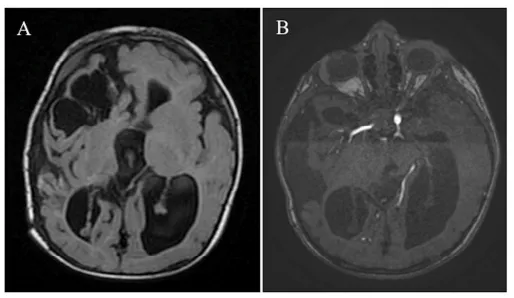

出生第1天,亨利被确认存在颅内血管病变,表现为囊状动脉瘤样结构,内部为搏动性血流。同日进行的磁共振血管成像(MRA)显示右侧额叶软脑膜动静脉瘘(PAVF),伴软脑膜静脉瘤样扩张,其内血流湍急,经扩张静脉引流入上矢状窦(图1C-E)。该病变还压迫同侧脑组织,导致局部脑实质萎缩。

亨利术后24个月随访未见晚期并发症(图4)。

在他4岁时的随访中,其神经功能与认知发育均达到满意水平。